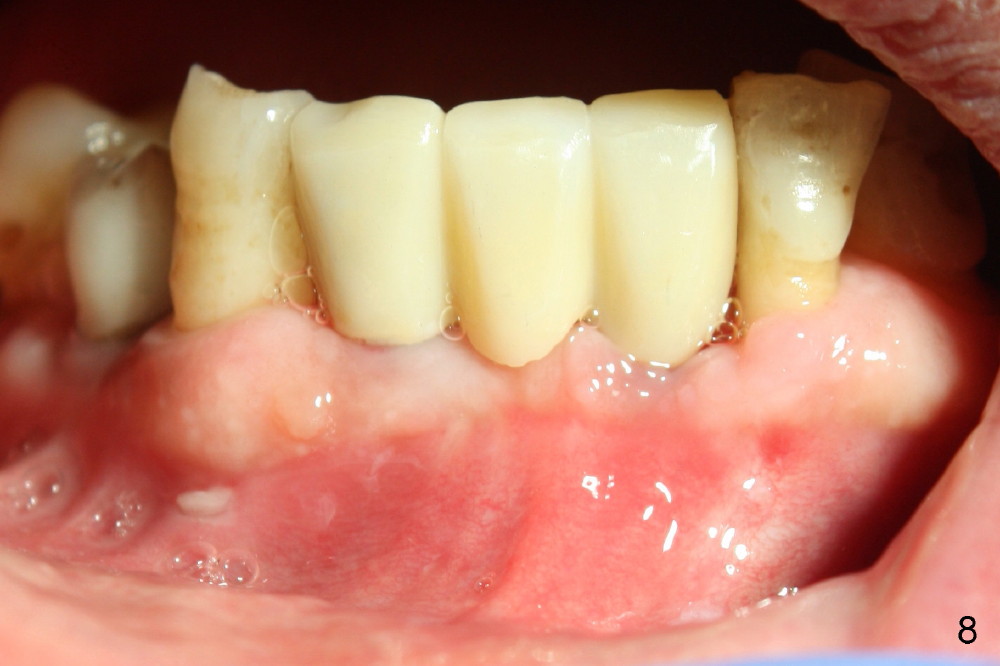

Fig.7 shows these two one piece implants immediately prior to cementation of the FPD (Fig.8). They are much more parallel to each other after prep, as compared to Fig.6. Fig.9 shows apparent bone growth around #24 implant (at the crest) 6,9 months post cementation and surgery, respectively. Orthodontic treatment will incorporate the fixed partial denture. Fig.10 shows that bone grows coronally (arrow) to cover 3 threads (from #6 thread to #3) at the site of #24 one year after functioning. There is mild buccal gingival infection involving #26 retainer. Preop CBCT is reviewed to determine whether it is related to potential thread exposure. It appears that at the sites of #24 (Fig.13,14) and 26 (Fig.11,12), 2.5 mm implant is more appropriate for the narrow ridge than 3.0 mm one. In fact, periimplantitis develops at #26 two years of absence of perio maintenance (because of atrial fibrillation with blood thinner; Fig.15, 3 years 7 months post cementation). Periimplantitis persists 4.5 months later. Although water pik is purchased, it is not used often because of low blowing force. If needed, remove the FPD atraumatically. Unwind the implant, clean the coronal threads with Titanium brush or remove the exposed threads and replant the implant with bone graft.